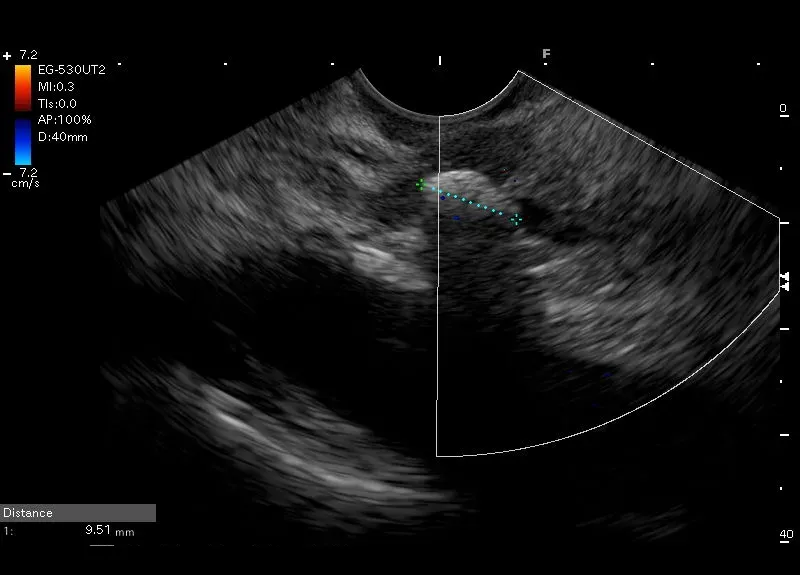

W świetle przybrodawkowego odcinka przewodu Wirsunga, tuż przy brodawce Vatera widoczne jest hyperechogeniczne, owalne ognisko wielości 9/7 mm z cieniem akustycznym – obraz odpowiadający złogowi w przewodzie Wirsunga.